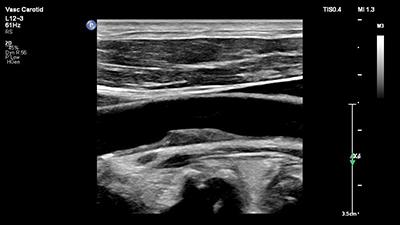

Flow Viewer

血流情報を3Dのようなレンダリングを使用して表示することで,従来のカラー画像に比べ,血管を明瞭に描出し、小血管の分岐や隣接血管との区別を容易にすることをサポートします。